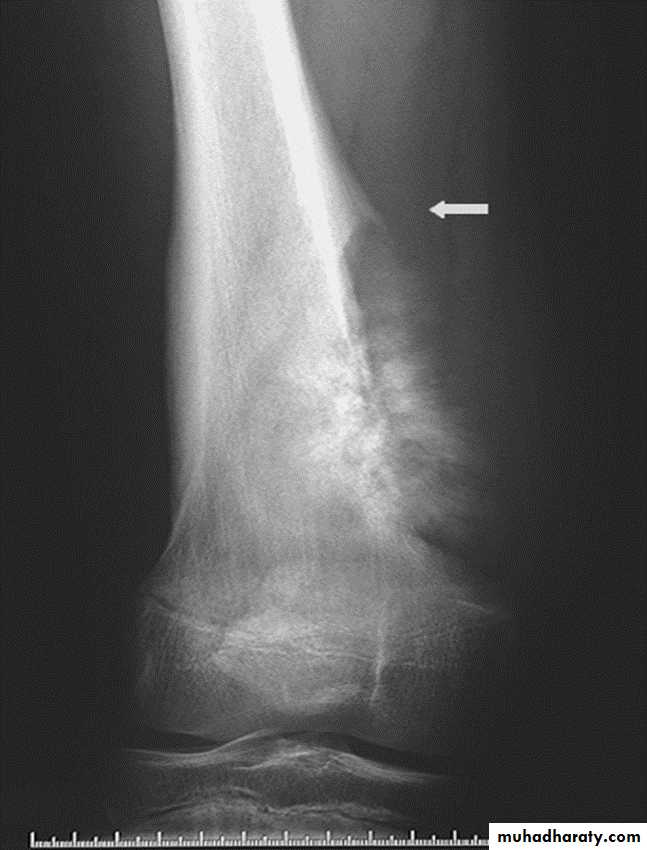

Solitary bone cyst:

Age: young adults & children.Site: long bones.

Findings: well-defined expanding lytic lesion.

A piece of cortical bone has broken off and descended through the serous fluid contained within the lesion and can be seen in the dependent portion of the lesion (arrow) as

a fallen fragment sign.

A fallen fragment sign is said to be pathgnomonic for

a unicameral bone cyst

Fallen fragment sign